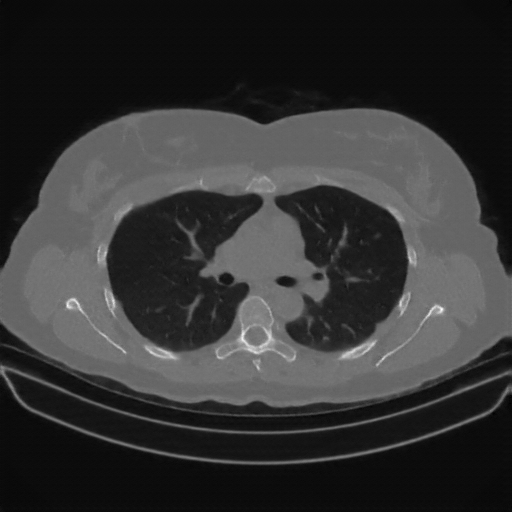

Reconstructed NATIVE CT scan (cycle consistency)

No window - Raw intensity values

Lung window (WL -600, WW 1500 β†’ Low βˆ’1350, High +150)

Mediastinum window (WL 40, WW 400 β†’ Low βˆ’160, High +240)